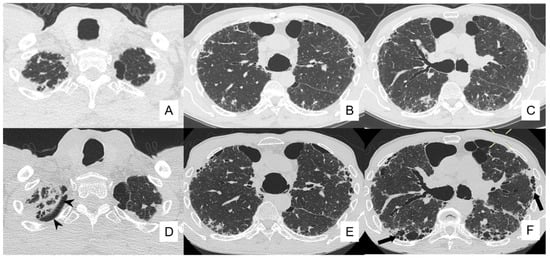

4.4. Pneumothorax